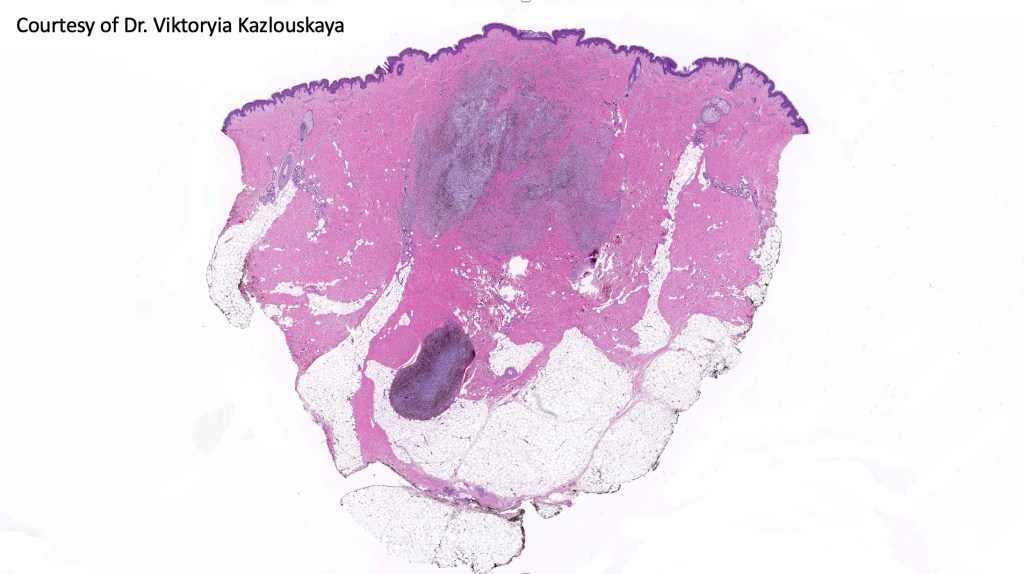

Cellular blue nevus

This uncommon most often devlops on the buttocks, sacrococcygeal region & distal extremities although it may be seen at just about any site. It shows a predilection for females and is diagnosed most often in the 2nd-4th decade. It presents as a blue-black/ or black nodule measuring 1-2 cm in dianeter. Similar to common blue nevus, the cellular variant can be encountered in a wide range of non-cutaneous locations.

Histological features

•Most characteristic is the dumbbell silhouette although a plague morphology may also be encountered

•Combined nevus variant

•Admixture of spindle cells, pigmented bipolar or dendritic cells & melanophages

•Cytoplasm is pale and nuclei are small with inconspicuous nucleoli

•An alveolar pattern is characteristic particularly with clear cell nodules

•Mitoses are typically very sparse or absent

•No atypical mitoses

•No Necrosis or lymphovascular invasion

•Multinucleate giant cells sometimes present

•Stromal fibrosis, myxoid change, vascular hyalinization with cyst formation are often seen

•Some tumors are composed spindle cells in a fascicular or neuronevoid pattern

•Perineural involvement may be seen

•Balloon cell change

•Desmoplastic variant

•Hypopigmented variant